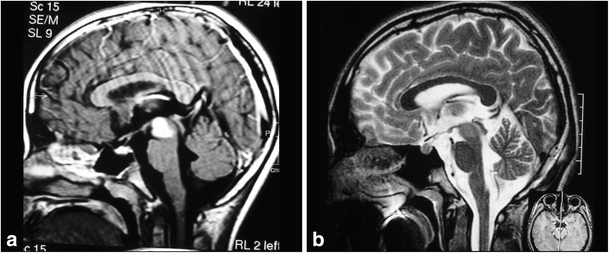

Fig. 14

figure 14

a, b 8-month-old patient with a large lesion in the anterior and superior portion of the pons, approached via orbito-fronto zygomatic via the supratrigeminal entry zone. c, d 6-month postoperative follow-up after complete resection of the lesion

Fig. 15

figure 15

a, b 10-year-old patient with tetraparesis. Tumor operated with a pre-sigmoid approach. c, d Postoperative control 10-year after gross total resection, showing no evidence of tumor